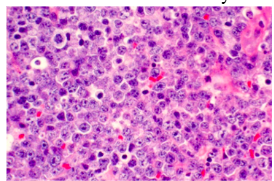

Non-Hodgkin’s Lymphoma pathology

-diffuse sheet of inflammatory cells

*Teeth “floating in air”

Histology:

*Diffuse small lymphocytes with “starry sky”

- sky = lymphocytes

- stars – macrophages